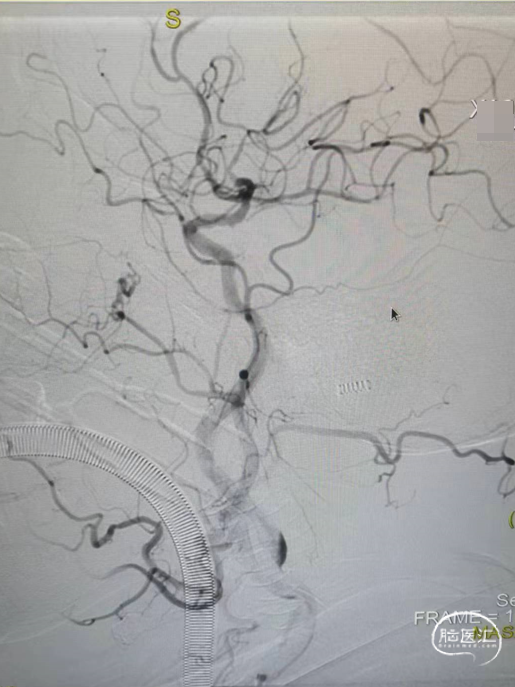

术后颈内动脉末端血流通常,左侧大脑前动脉和大脑中动脉显影正常。

取出的血栓。